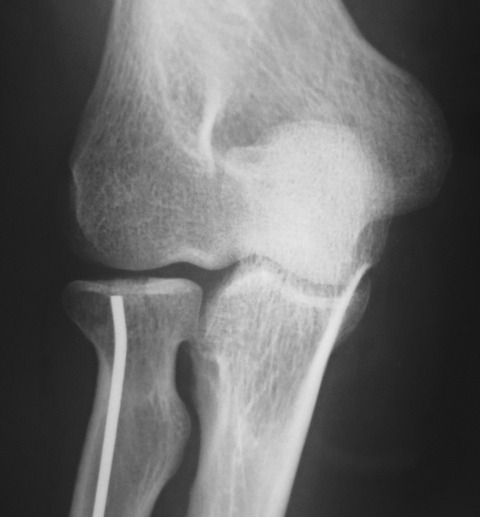

今日の午後は橈骨頭骨折の手術を行いました。単純X線像では分かりにくいのですが、CTを再構成した前額断像では関節面中央のみが陥没しているタイプの骨折でした。

比較的橈骨頚部の連続性は保たれていたので、橈骨頚部骨折と同様のK-wireを用いた整復・固定術を施行しました。今回使用したK-wireは2.0mmです。

まず、橈骨茎状突起先端の直上に約1cmの切開を加えて皮下を鈍的に剥離して橈骨茎状突起部を展開しました。橈骨神経浅枝損傷を避けるためにエアターニケットを使用します。

2.0 K-wireで皮質骨を開窓してから一旦抜去します。K-wireのお尻側の先が鈍な方を先頭にして、再度橈骨内に刺入します。この時にK-wireの先端を僅かに曲げておきます。

ハンマーで叩打しながら橈骨内を中枢方向に進めていきます。橈骨骨幹部を過ぎると急に抵抗が無くなり、あっという間に橈骨頚部に到達するので叩き過ぎに注意します。

橈骨頚部に到達した時点で、先ほど曲げたK-wire先端の方向を微調整します。橈骨茎状突起部のK-wireの断端は皮下に埋没しました。橈骨神経浅枝に接触しないように位置を調整します。

今日の手術も10分程度で終了しました。低侵襲なのに得られるメリットが大きいので良い手術だと思います。